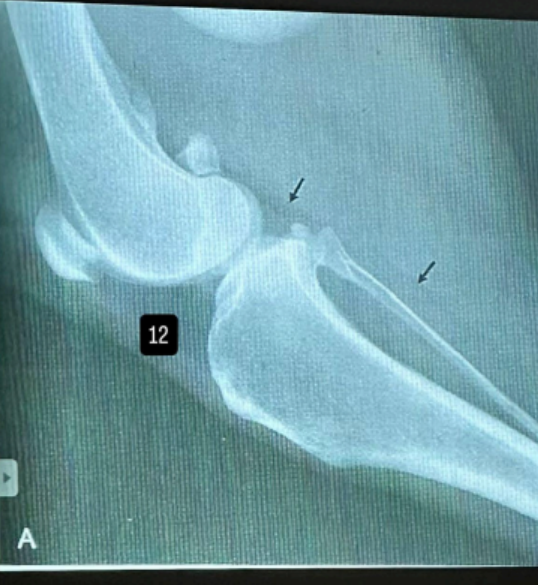

czym jest OCD?

występuje głównie w stawie skokowym ,kolanowym, łokciowym a w 74% wszystkich przypadków OCD, w stawie ramiennym, jest to zaburzenie kostnienia śródchrzęstnego, prowadzącego do degradacji chrząstki,